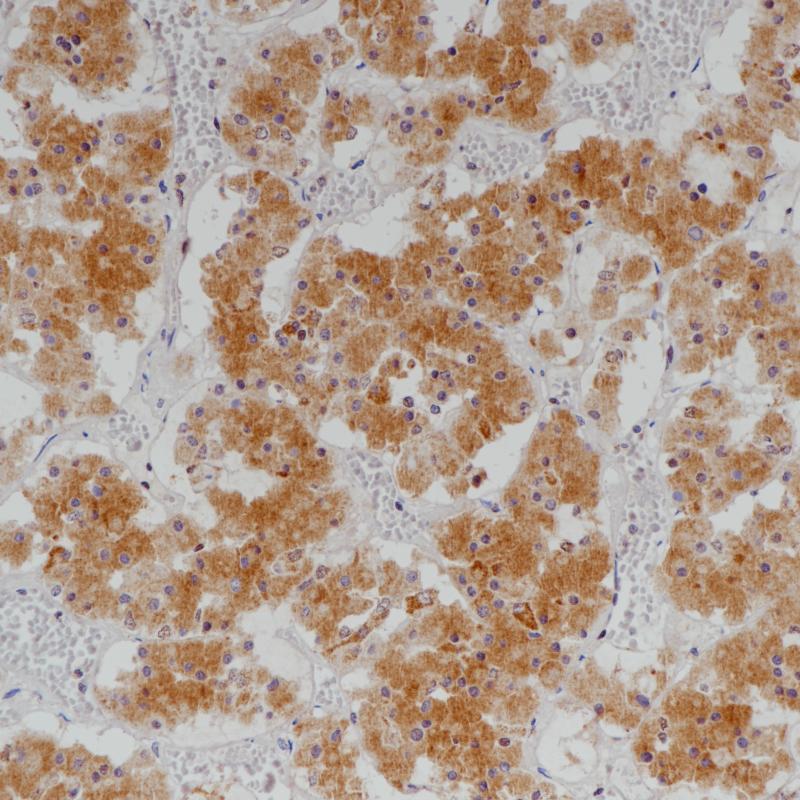

垂体前叶Growth Hormone(BPM6190)染色

生长激素(GH),促生长激素,是负责调节全身生长的主要激素,在有机代谢中也很重要。它是由垂体前叶的嗜酸性或促生长细胞合成的。生长激素通过促进肝脏产生体细胞素间接刺激生长,而体细胞素直接作用于骨骼和软组织导致生长。生长激素对肝脏、脂肪组织和肌肉产生直接的代谢影响。一般来说,生长激素促进蛋白质合成,保存碳水化合物,消耗脂肪储存。

推荐使用人类生长激素(HGH)检测正常和肿瘤组织中感兴趣的特异性抗原,作为常规组织病理学的辅助手段。

阳性对照

脑垂体

亚细胞定位

细胞质